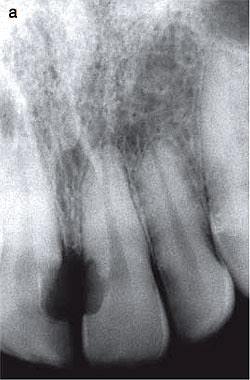

ตัวอย่างทางคลินิกของ Class 1 สังเกตซี่ 12 บริเวณขอบเหงือกที่มีลักษณะแดงและไม่เรียบ

film 12 แสดงรอยโรค Invasive cervical resorption Class 1